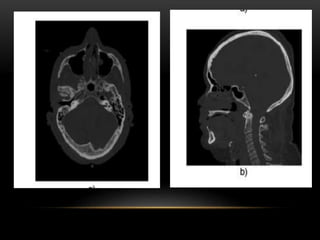

• TOMOGRAFIA AXIAL:

• DURANTE LA OBTENCION DE DATOS , LA MESA DEL PACIENTE

PERMANECE INMOVIL , CADA REVOLUCION DEL TUBO DE RX

ALREDEDOR DEL PACIENTE PRODUCE UN UNICO CONJUNTO DE

DATOS ( CORTE).

RECONSTRUCCIÓN MULTIPLANAR MPR

• No es reconstrucción tridimensional

• Es una deformación geométrica de los datos.

• Crea una imagen bidimensional con un punto de vista tridimensional

• Las reconstrucciones multiplanares deben de ser calculadas a partir de voxeles isotropicos (